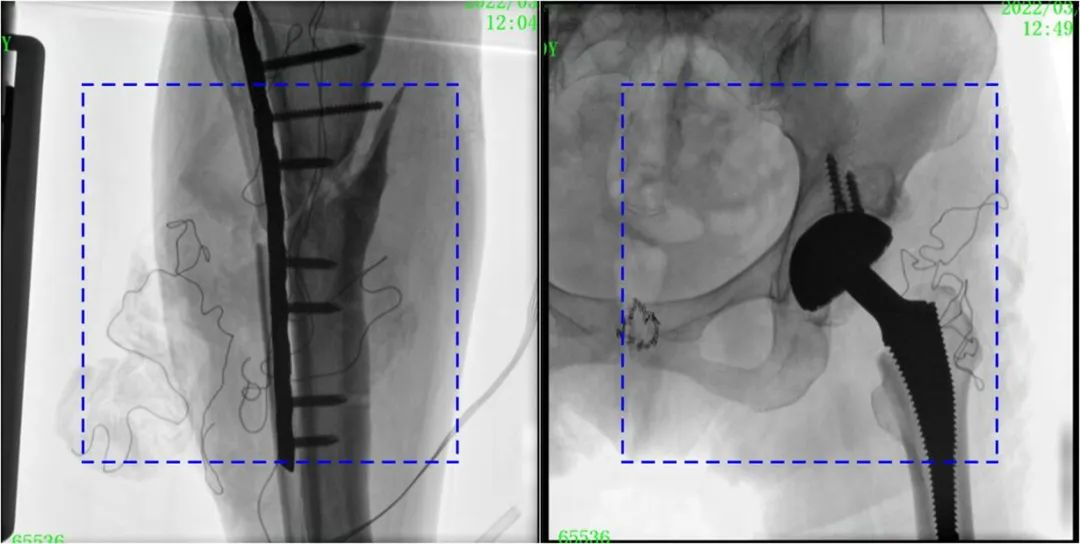

與傳統(tǒng)的21CM×21CM成像尺寸相比,普愛(ài)醫(yī)療大平板一體式C形臂具有30CM×30CM更大成像尺寸,能夠一次成像5.5節(jié)椎體,呈現(xiàn)更全面的影像信息,即便是手術(shù)經(jīng)驗(yàn)不豐富的年輕醫(yī)生也能通過(guò)圖像迅速判斷椎體節(jié)段、定位手術(shù)部位,避免因?yàn)橐曇安蛔愣斐傻亩啻味ㄎ?、反?fù)曝光,提高效率的同時(shí)避免過(guò)量攝入輻射。

普愛(ài)醫(yī)療大平板一體式C形臂圖像與傳統(tǒng)圖像對(duì)比(藍(lán)色虛線內(nèi)為傳統(tǒng)21CM×21CM平板的成像區(qū)域)